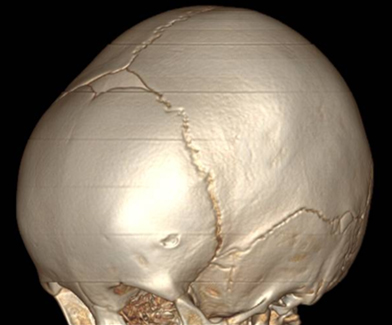

眼眶CT不仅能显示囊肿大小,部位,肿块的结构特点,还可以观察到囊肿和眶骨之间的位置关系,以及眶壁是否有压迫凹陷或者增生,如图5所示。

图5:箭头所指方向可以看到在圆润的颅骨表面可以看到一个缺口,对颅骨明显的侵袭压迫,造成局部颅骨缺损。